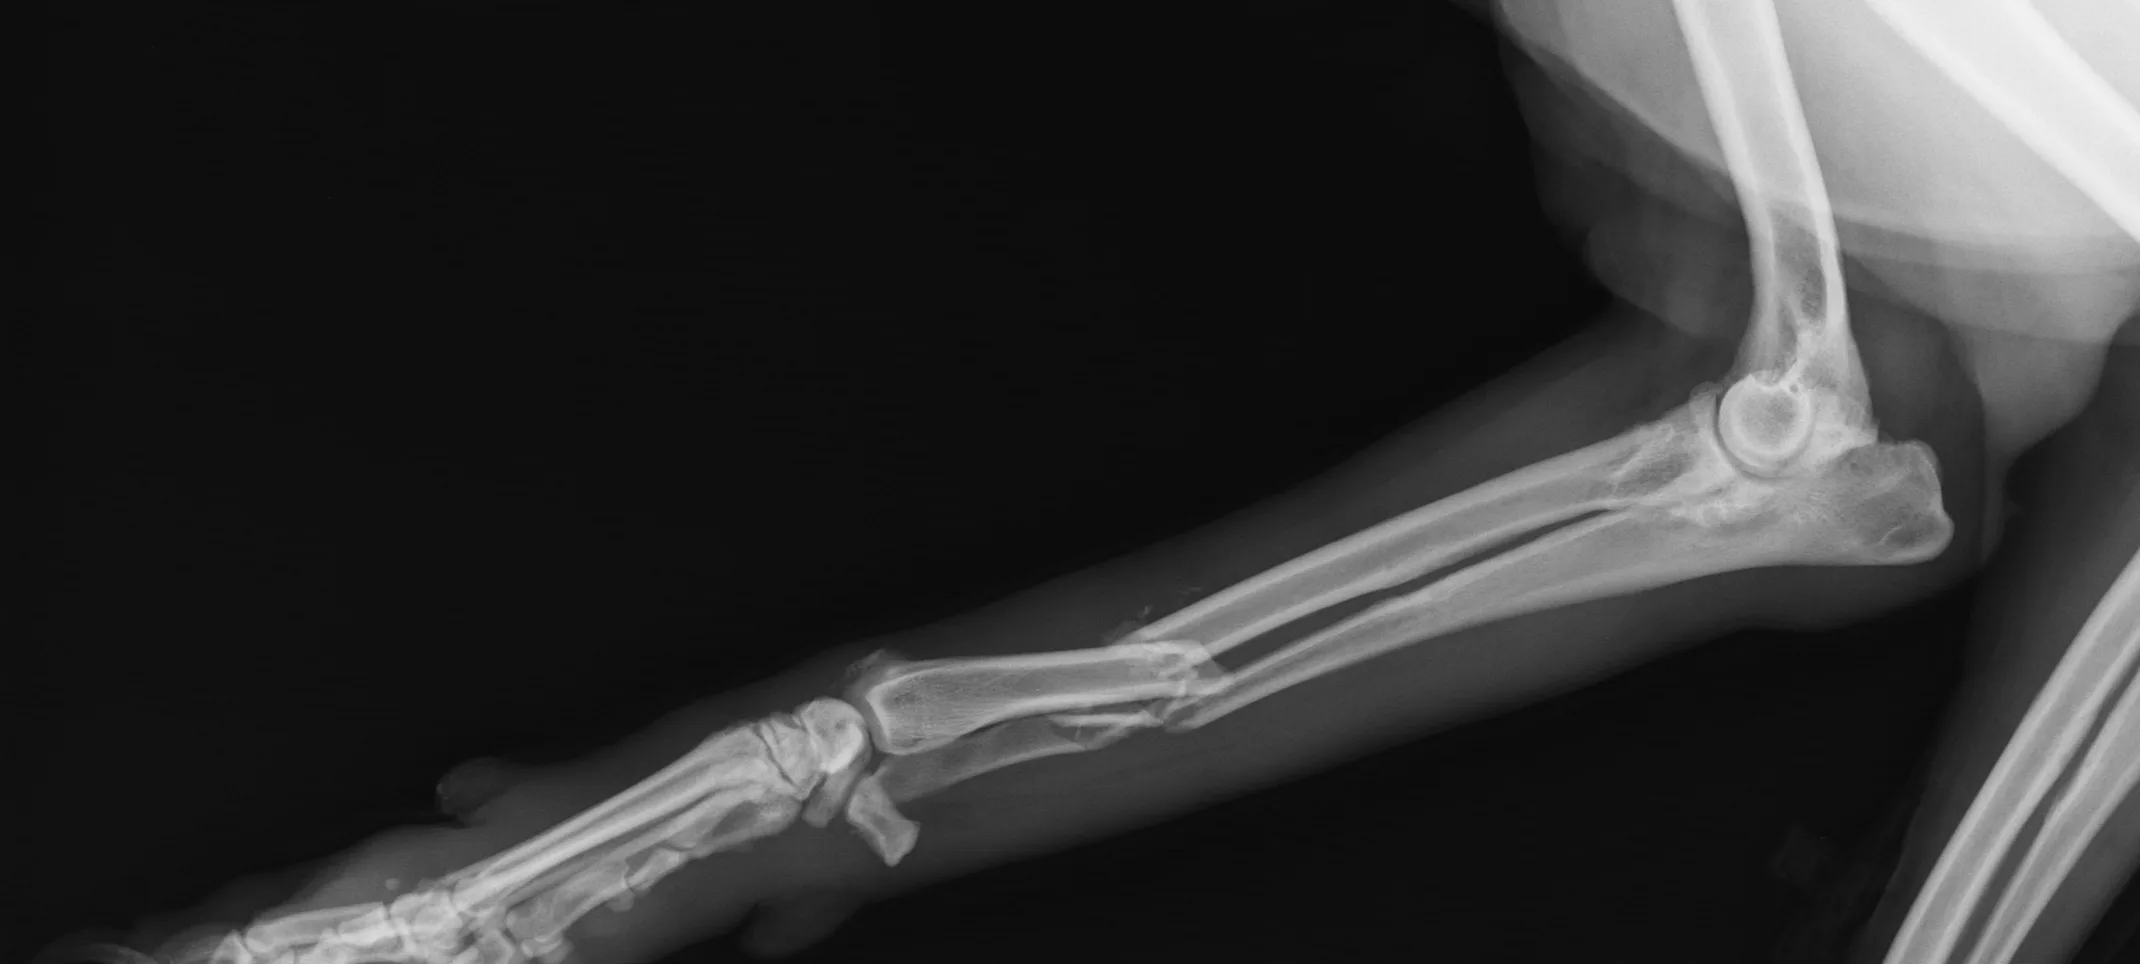

Every effort is made to prevent disease progression. Our standard of patient care includes regular check-ins to ensure remission. Long-term periodical scans may include radiographs, ultrasound, and/or CT.